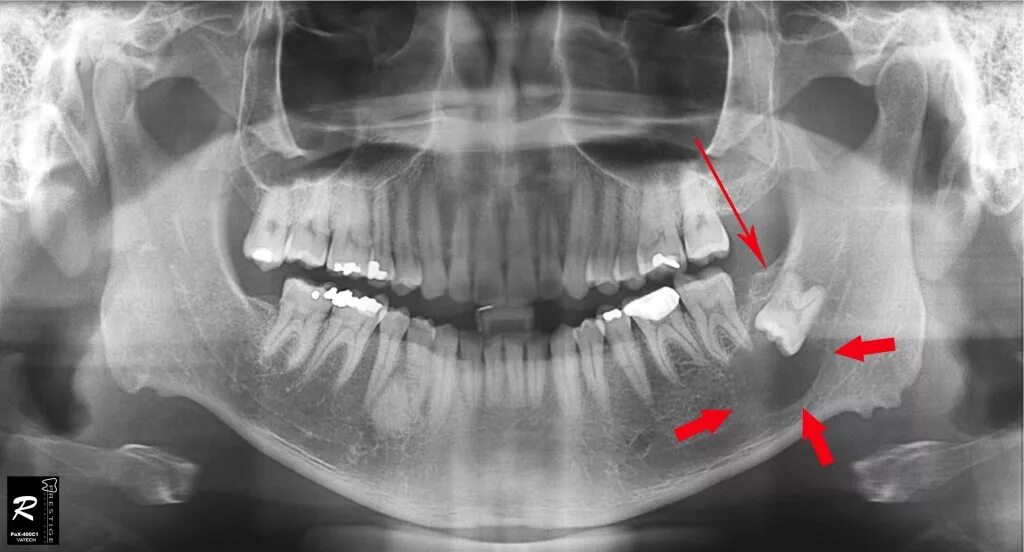

Снимок верхней и нижней челюсти